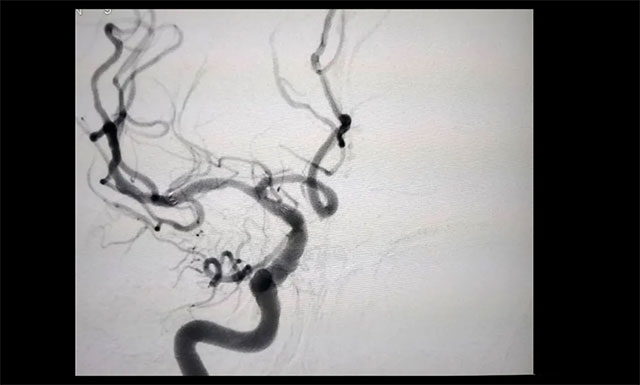

▲ 治疗后狭窄明显改善

经过与医院脑血管病病区主任张琪博士团队开展评估会诊,在医院DSA系统的支持下,由张琪博士为胡老伯行右侧大脑中动脉球囊扩张及支架置入手术。术中造影观察可见,狭窄明显改善,血流也随即恢复了通畅。